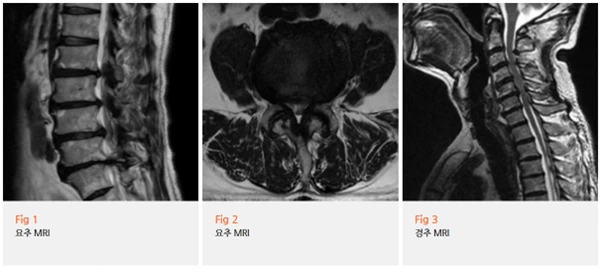

MRI 결과를 보니,

과거 수술 부위 상단인 요추 4-5번에 심한 협착이 진행되어 있었고

전체적으로 퇴행성 디스크 변화가 허리 마디마다 확인됐어요.

근전도 검사에서도 하위 요추 신경근병증이 확인됐고,

이미 만성화된 신경 손상 가능성이 높은 상태였습니다.